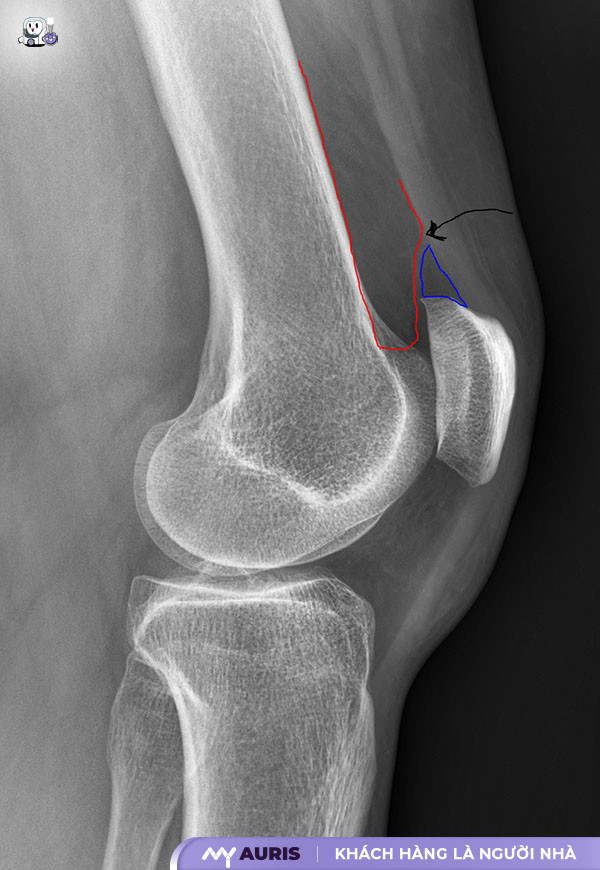

Tràn dịch khớp gối là tình trạng dịch khớp gối tích tụ quá nhiều trong bao hoạt dịch. Dịch khớp bình thường có vai trò bôi trơn, giảm ma sát, nuôi dưỡng sụn khớp. Tuy nhiên, khi khớp gối bị viêm, chấn thương hoặc mắc bệnh lý, lượng dịch khớp sẽ tăng lên gây sưng, đau, hạn chế vận động. Tình trạng này ảnh hưởng đến sinh hoạt hàng ngày, gây khó khăn khi di chuyển, làm việc.

Chấn thương khớp gối: Chấn thương như bong gân, đứt dây chằng, gãy xương hoặc va đập mạnh có thể dẫn đến viêm, sưng và tràn dịch khớp gối. Bệnh lý đầu gối do chấn thương cần được điều trị kịp thời để tránh biến chứng.

Tràn dịch khớp gối xảy ra khi dịch khớp gối tích tụ quá nhiều, gây sưng phù nề khớp gối. Dịch khớp gối có vai trò bôi trơn, giảm ma sát. Tuy nhiên, khi bị viêm, chấn thương hoặc bệnh lý, lượng dịch này tăng lên, gây đau, hạn chế vận động. Triệu chứng thường gặp bao gồm: sưng tấy cục bộ, đau nhức khi vận động, hạn chế cử động khớp, cảm giác nặng nề ở đầu gối, khớp gối ấm nóng.

Chấn thương khớp gối, như bong gân, đứt dây chằng, cũng gây đau, sưng, tràn dịch. Tuy nhiên, chấn thương thường xảy ra đột ngột sau va đập, té ngã. Phân biệt bằng cách xem xét tiền sử chấn thương.